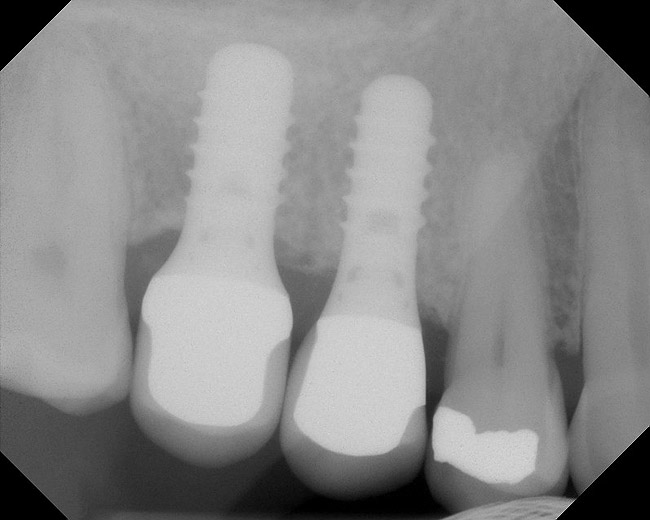

Figure 19  Radiographic view of implant placed simultaneously with sinus bone grafting in site No. 3.

Figure 19